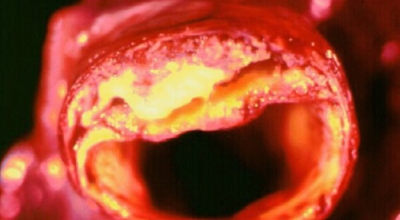

고혈압은 수축기 혈압 140mmHg 이상이거나 완압기 혈압 90mmHg 이상인 경우를 말해요. 관상동맥질환, 뇌졸중, 신부전 과 같은 가지가지 합병증을 일으킵니다. 고혈압은 2019년 질병관리청 자료에 근거하면 30세 이상 남자 31.1%, 여자 23.1%가 가진 만성질환으로 2015년부터 1,100만명을 돌파했습니다. 고혈압으로 말미암아 오는 합병증은 고혈압의 혈압이 높은 것으로도 위험하지만 합병증까지 생긴다면 더 심각해요.

합병증이 오시면 심한다면 생명의 위협까지 가할 수 있어 관리가 아주 중요해요. 고혈압은 뇌에 영향을 주어 뇌경색이나 뇌출혈, 치매를 발생시킬 수 있습니다. 눈에도 영향을 주어 망막증이나 심하게는 실명까지 갈 수 있다고 하며 심장에도 무리를 주어 심부전증, 협심증, 심근경색까지 생기게 될 수 있답니다.